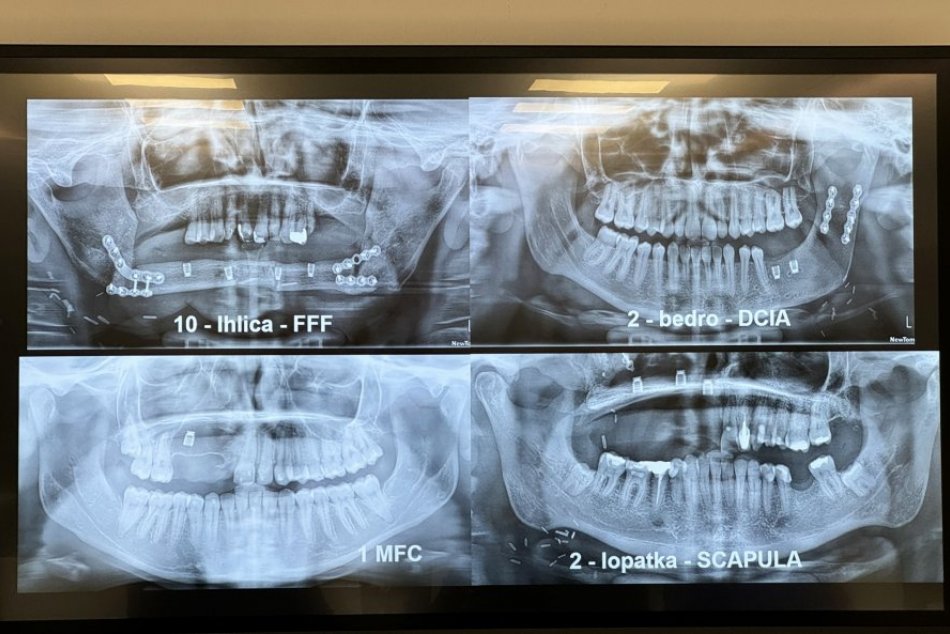

Chirurgická časť, implantácia a modelovanie mäkkých tkanív prebieha na klinike, protetická časť v spolupráci s externým protetikom a laboratóriom. Pacientom vykonávajú náhrady čeľusti a sánky z ich vlastného kostného tkaniva z inej časti tela – lopatky, bedra alebo ihlice predkolenia.

Odborníci z Kliniky maxilofaciálnej chirurgie Rooseveltovej nemocnice v Banskej Bystrici vedia pacientom, ktorí prišli o časť tváre, okrem rekonštrukcie čeľusti implantovať už aj zuby. Rekonštrukcie s osádzaním dentálnych implantátov začali v tejto nemocnici vykonávať medzi prvými na Slovensku. Túto novinku, vďaka ktorej sa pacienti môžu zaradiť do bežného života, predstavili v stredu v nemocnici.

„Naša práca je špeciálna ešte v tom, že dentálne implantáty, ktoré umiestňujeme do mikrovaskulárnych lalokov sú menšej veľkosti, ako boli inde doposiaľ používané. Tým šetríme transplantované tkanivá, výkony sú menej invazívne a pacientmi lepšie tolerovateľné,“ zdôraznil primár kliniky Rastislav Slávik. Krátke dentálne implantáty zavádzajú na klinike ako jediní na Slovensku.